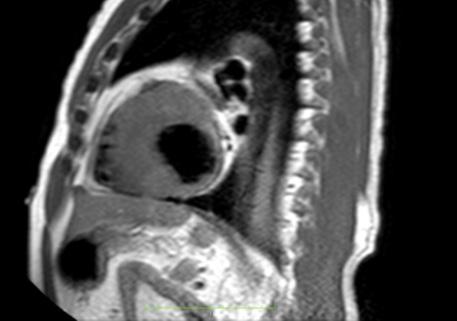

• La resonancia magnética cardíaca

Cardiovascular Disease Fellowship Program, St. Figure 2: Vista sagital de la resonancia magnética cardíaca IVS engrosamiento de 3,0 cm e infiltración fibrosa septal.

posterior mostró un engrosamiento del tabique interventricular de 3,0 cm, así como una infiltración fibrosa del tabique confirmando el diagnóstico de MCH.

Figure 3: Vista axial de resonancia magnética cardíaca IVS engrosamiento 3.0cm e infiltración fibrosa septal.